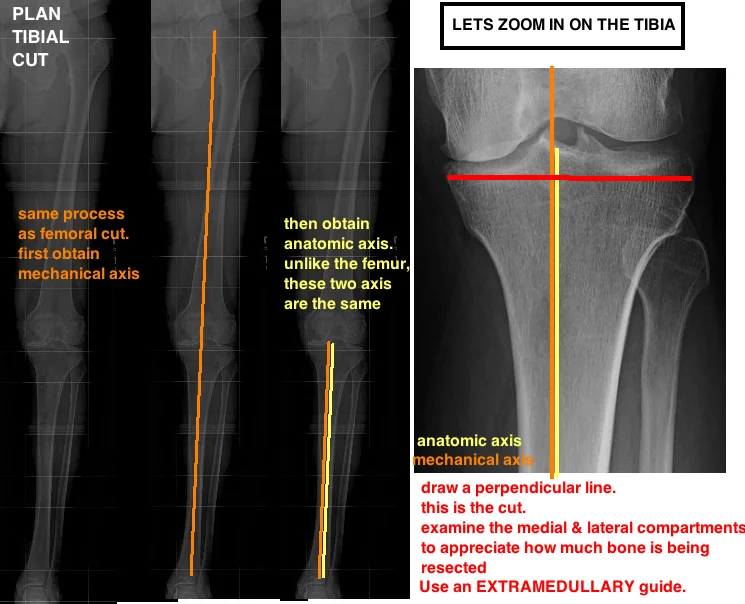

plan tibial cut for tka measuring the anatomic axis